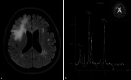

We here report on a 60-year-old woman with familial Mediterranean fever (FMF) who developed cognitive impairment 16 years after initial diagnosis. On MRI, a new extensive white matter lesion in the right frontal lobe with mild local mass effect but without contrast enhancement was detectable and classified as a tumefactive lesion. Additional MR spectroscopy showed markedly increased choline levels accompanied by a significant lactate peak, highly suggestive of a low-florid demyelinating process. Although diffuse central nervous system (CNS) lesions have been described in single FMF cases, tumefactive lesions have not been observed in FMF patients without concomitant multiple sclerosis. In summary, this case highlights rare differential diagnoses of atypical, inflammatory CNS lesions and the clinical utility of MR spectroscopy.